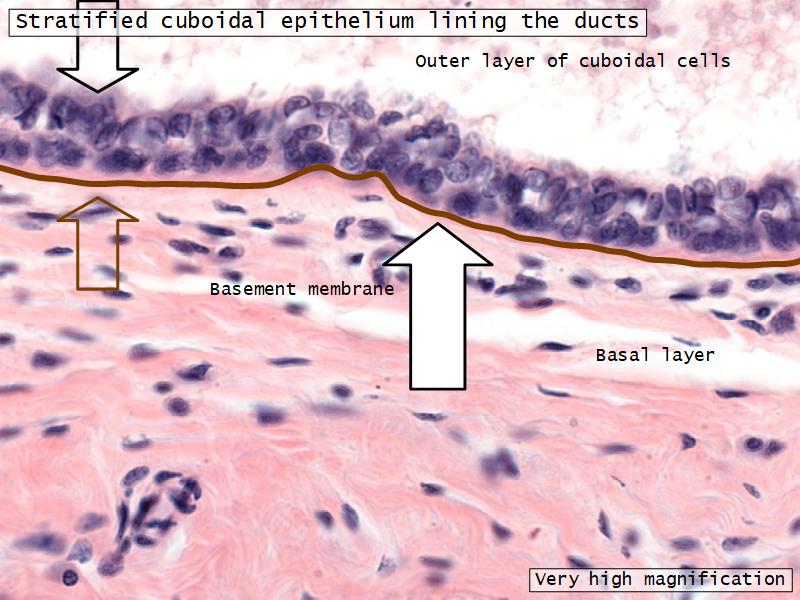

What epithelium are associated with ducts?Q03 - 3

What epithelium are associated with ducts?

Cuboidal epithelium

Q06: Epithelium

- Is bordered by a ______.

- Rests on a ______.

Q06: Epithelium

- Is bordered by a lumen.

- Rests on a basement membrane.

- Lactiferous ducts

- Stratified cuboidal

- Myoepithelial cells

- Underlie lactiferous ducts in most areas

- Basal lamina

- Separate epithelial components from stroma